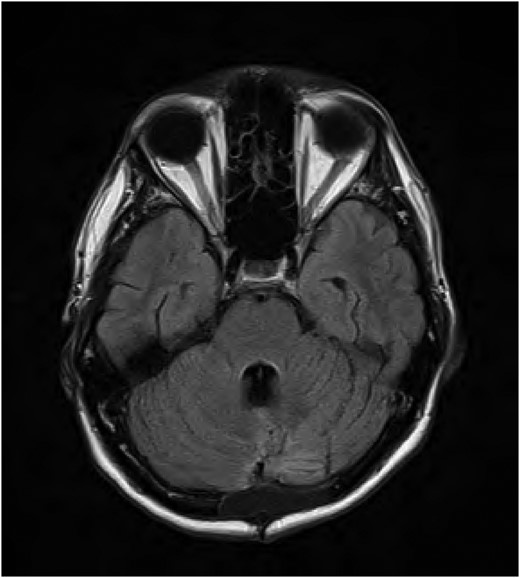

He was reviewed by the ophthalmology team which confirmed the examination findings and advised eye patch and moisturizing eye drops. The patient had a repeat MRI brain on 11 August 2015 which showed interval decrease in the focal hyperintensity surrounding the fourth ventricle and dorsal pons (Fig. 2). He was subsequently discharged from the hospital. On review in clinic on 11 November 2015, there had been significant improvement in his sixth cranial nerve function, but there was no improvement in his bilateral facial palsies.

FLAIR MRI brain follow-up showing improvement of the signal abnormality in the fourth ventricle.